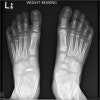

X-ray에서 특징적으로 주상골이 편평화, 왜소화되고 경화상을 보이며 그 가장자리는 고르지 못하고, 분열되는 경우도 있습니다.

X-ray : 쾰러병(Köhler disease, Kohler disease)